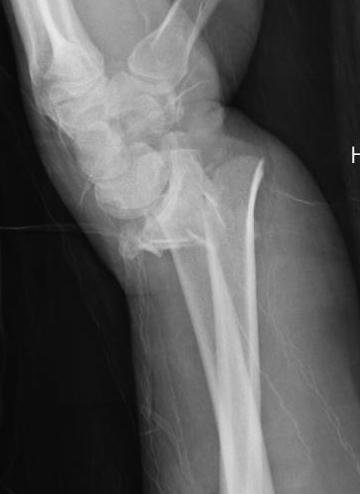

Distal radius fracture with shortening and dorsal tilt

Articular incongruency > 2 mm

Sigmoid notch disruption and DRUJ instability